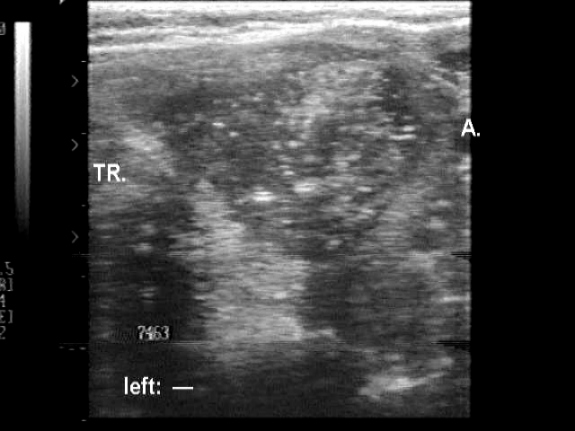

Medullary carcinoma (histological diagnosis) - case 1774

This tumor contains numerous amyloid deposits. The images were gained with an older equipment, therefore the bright granules within the echonormal background of the patches are larger because of the low quality resolution.